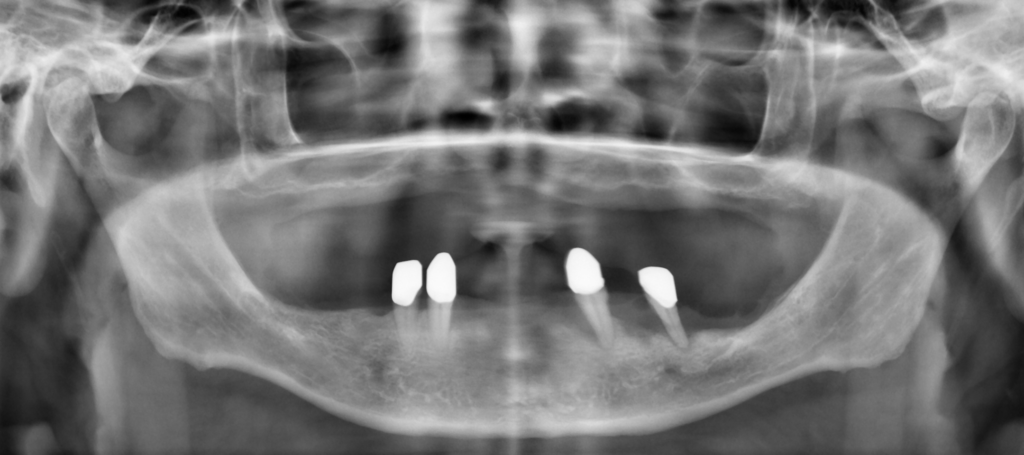

Vertikale Knochenaugmentation – Realität oder Illusion?

Knochendefekte gehören heute zum klinischen Alltag der implantologischen Praxis. Langjähriger Zahnverlust, Trauma oder entzündliche Erkrankungen können zu ausgeprägten horizontalen und vertikalen Defiziten des Alveolarfortsatzes führen, die eine rekonstruktive Hartgewebsaugmentation erforderlich machen.